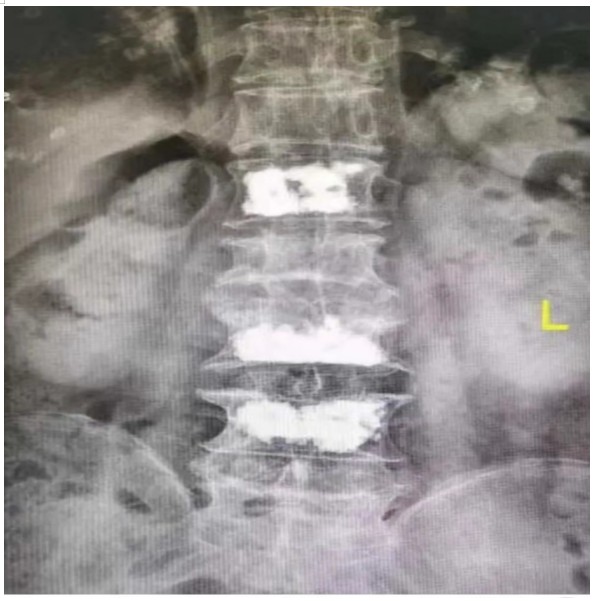

原來,89歲的占大爺因在家勞作時突發(fā)腰背部疼痛難忍、腰部無法直立,行走困難,在家臥床休息兩周后疼痛仍未減輕,于是來到衡陽市中心醫(yī)院脊柱外科就診。接診的盛凱醫(yī)師仔細查體結(jié)合磁共振檢查發(fā)現(xiàn),占大爺腰椎L1、L3、L4有椎體壓縮骨折,診斷為腰椎體壓縮骨折、重度骨質(zhì)疏松癥。錢軍博士團隊結(jié)合對病人多椎體的骨折做出了細致的評估,經(jīng)過認真分析研究,決定為患者實施腰椎體壓縮性骨折經(jīng)皮穿刺椎體成形術(shù)(PVP)。手術(shù)當天,醫(yī)師團隊在C-臂監(jiān)視器透視下,分別定位L1、L3、L4雙側(cè)椎弓根位置,以標記穿刺點為中心做3mm切開,在透視下注入骨水泥,再次透視見骨水泥位置良好,順利完成手術(shù)。